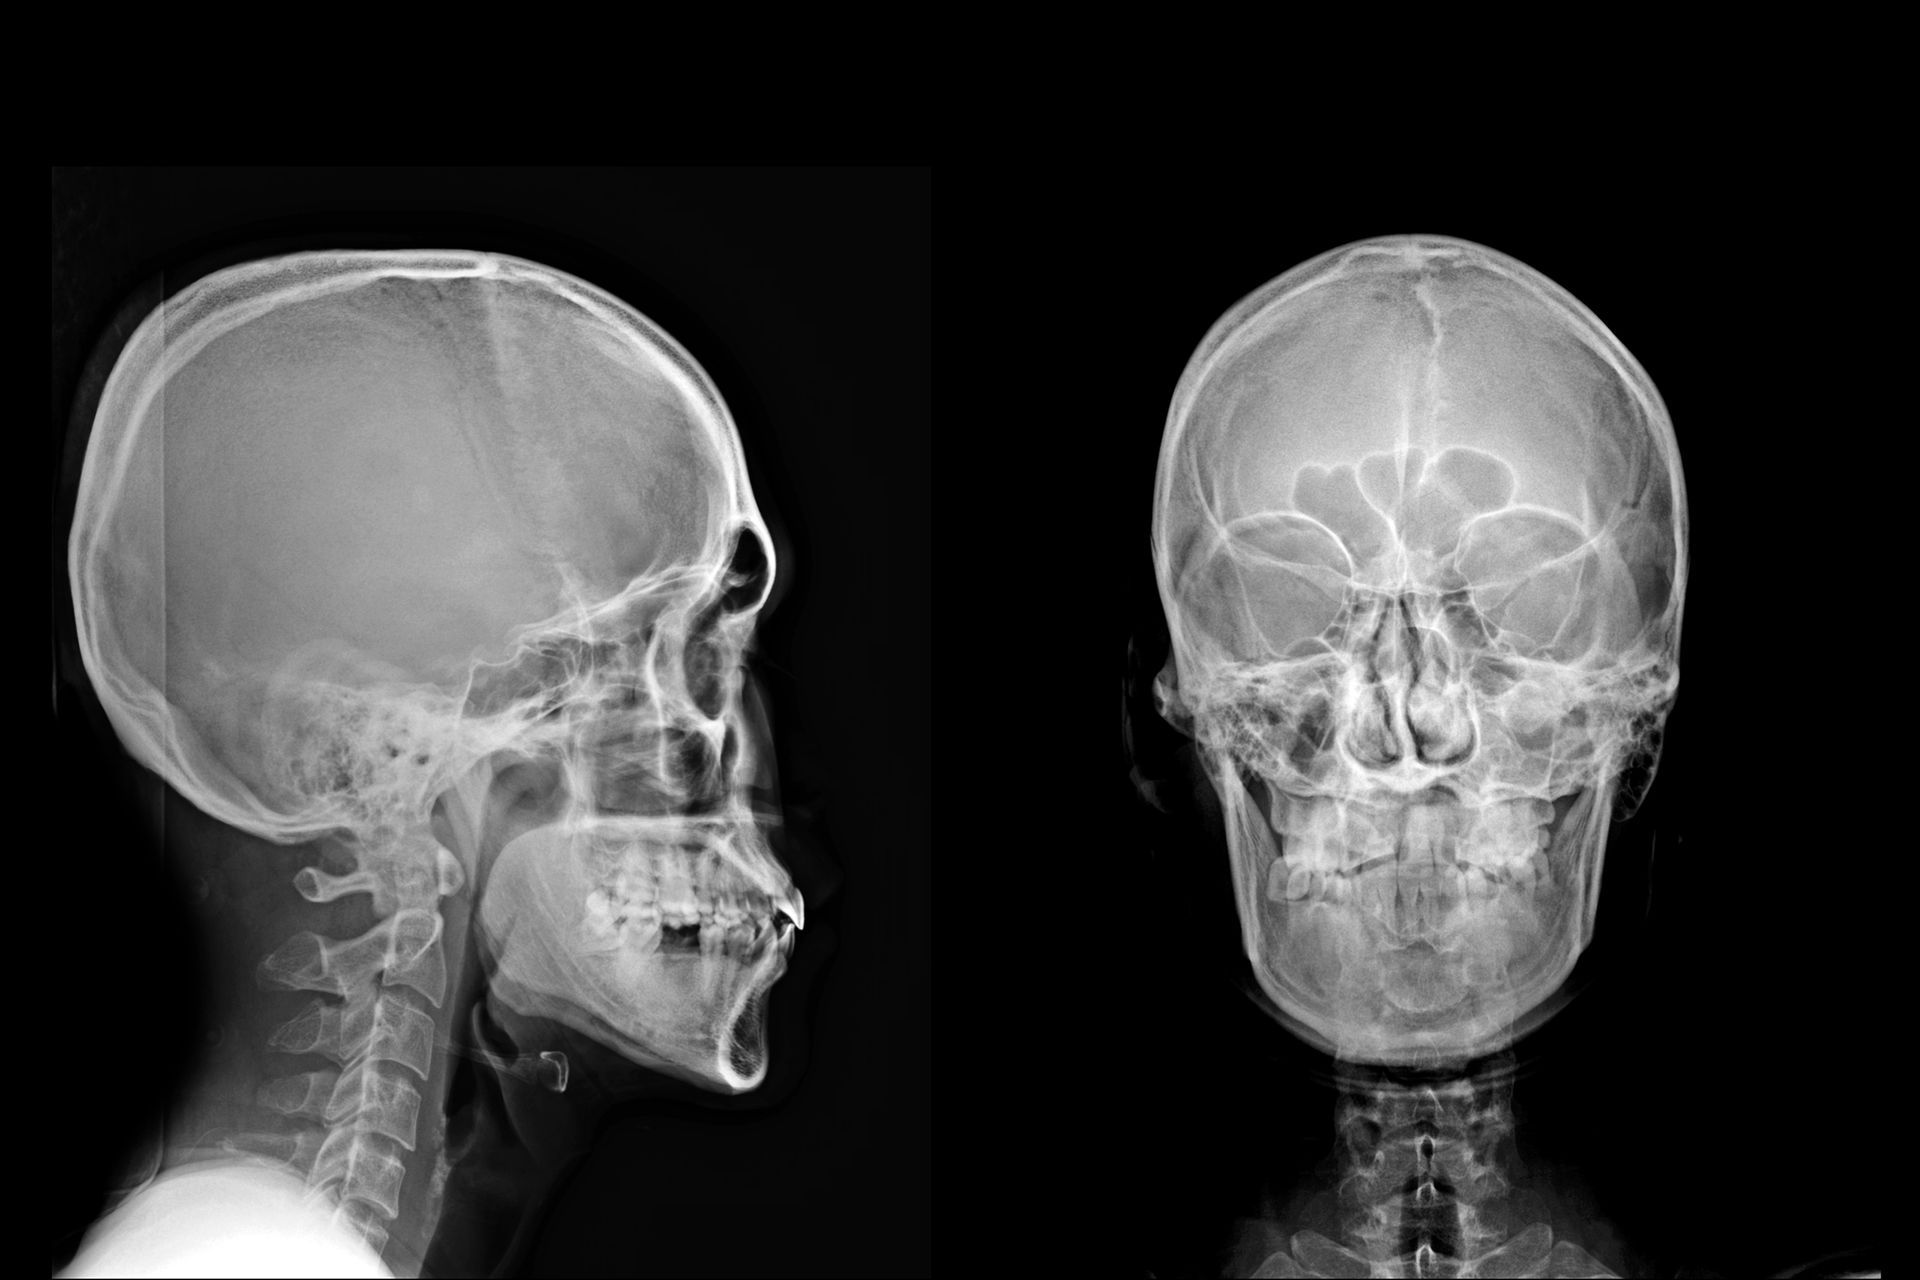

Telecranio: funzione diagnostica e analisi cefalometrica

Il telecranio è un esame di riferimento nella valutazione ortodontica, poiché consente di analizzare con precisione le proporzioni del cranio, la posizione delle arcate dentarie e i rapporti scheletrici. Viene eseguito generalmente in proiezione laterale, ma può includere anche viste postero-anteriori o antero-posteriori quando l’analisi richiede una valutazione più completa delle simmetrie facciali. La procedura prevede il posizionamento del paziente all’interno del craniostato, che garantisce il corretto allineamento della testa grazie a specifici punti di appoggio auricolari e frontali.

Una corretta intercuspidazione è fondamentale affinché le immagini rappresentino fedelmente la relazione occlusale. Attraverso questo esame, parte integrante della Panoramica Dentale e Telecranio a Casarano (LE), è possibile rilevare eventuali malocclusioni, morsi inversi e discrepanze tra mascella e mandibola, oltre a valutare la crescita scheletrica nei pazienti in età evolutiva. La tecnologia digitale consente di ottenere immagini nitide e misurabili, utili per elaborare un piano di trattamento ortodontico basato su dati oggettivi e perfettamente riproducibili.